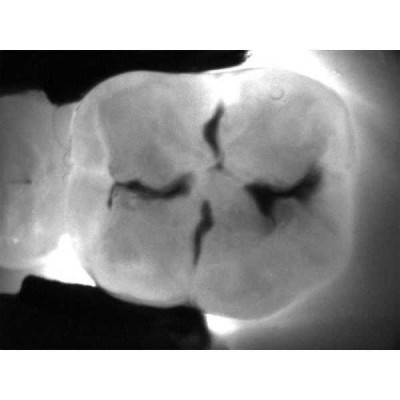

Весь секрет заключается в технологии DIFOTI за счет генерируемого прибором трансилюминационного (трансиллюминация - яркое сквозное освещение) лазерного излучения в нерентгеновском диапазоне волн. Если объяснять это простым языком, то это излучение, занимающее диапазон между видимым светом и рентгеновским диапазоном, которое проходит сквозь твердые ткани зуба, при этом области, не пропускающие свет (например, области кариозного поражения) отображаются в виде затемненных на общем фоне участков.

Рентгенограммы и снимки, полученные с помощью KaVo DIAGNOcam, относятся к методам диагностики, прекрасно дополняющим друг друга. С помощью рентгенологической диагностики Вы в дальнейшем сможете беспрепятственно проверить и дополнить данные KaVo DIAGNOcam, исключив часть рентгеновского излучения для пациента. На снимках отчетливо визуализируются структуры коронковой части зуба, располагающиеся выше уровня десневого края. Таким образом, становится возможным раннее распознавание кариеса и проведение профилактического, малоинвазивного лечения. Ваши пациенты будут в восторге!

- Выявление трещин эмали без применения стоматологического микроскопа.

- Отсутствие наложения теней в контактной области, характерного для рентгенограммы задний план обеспечивает надежную визуализацию.